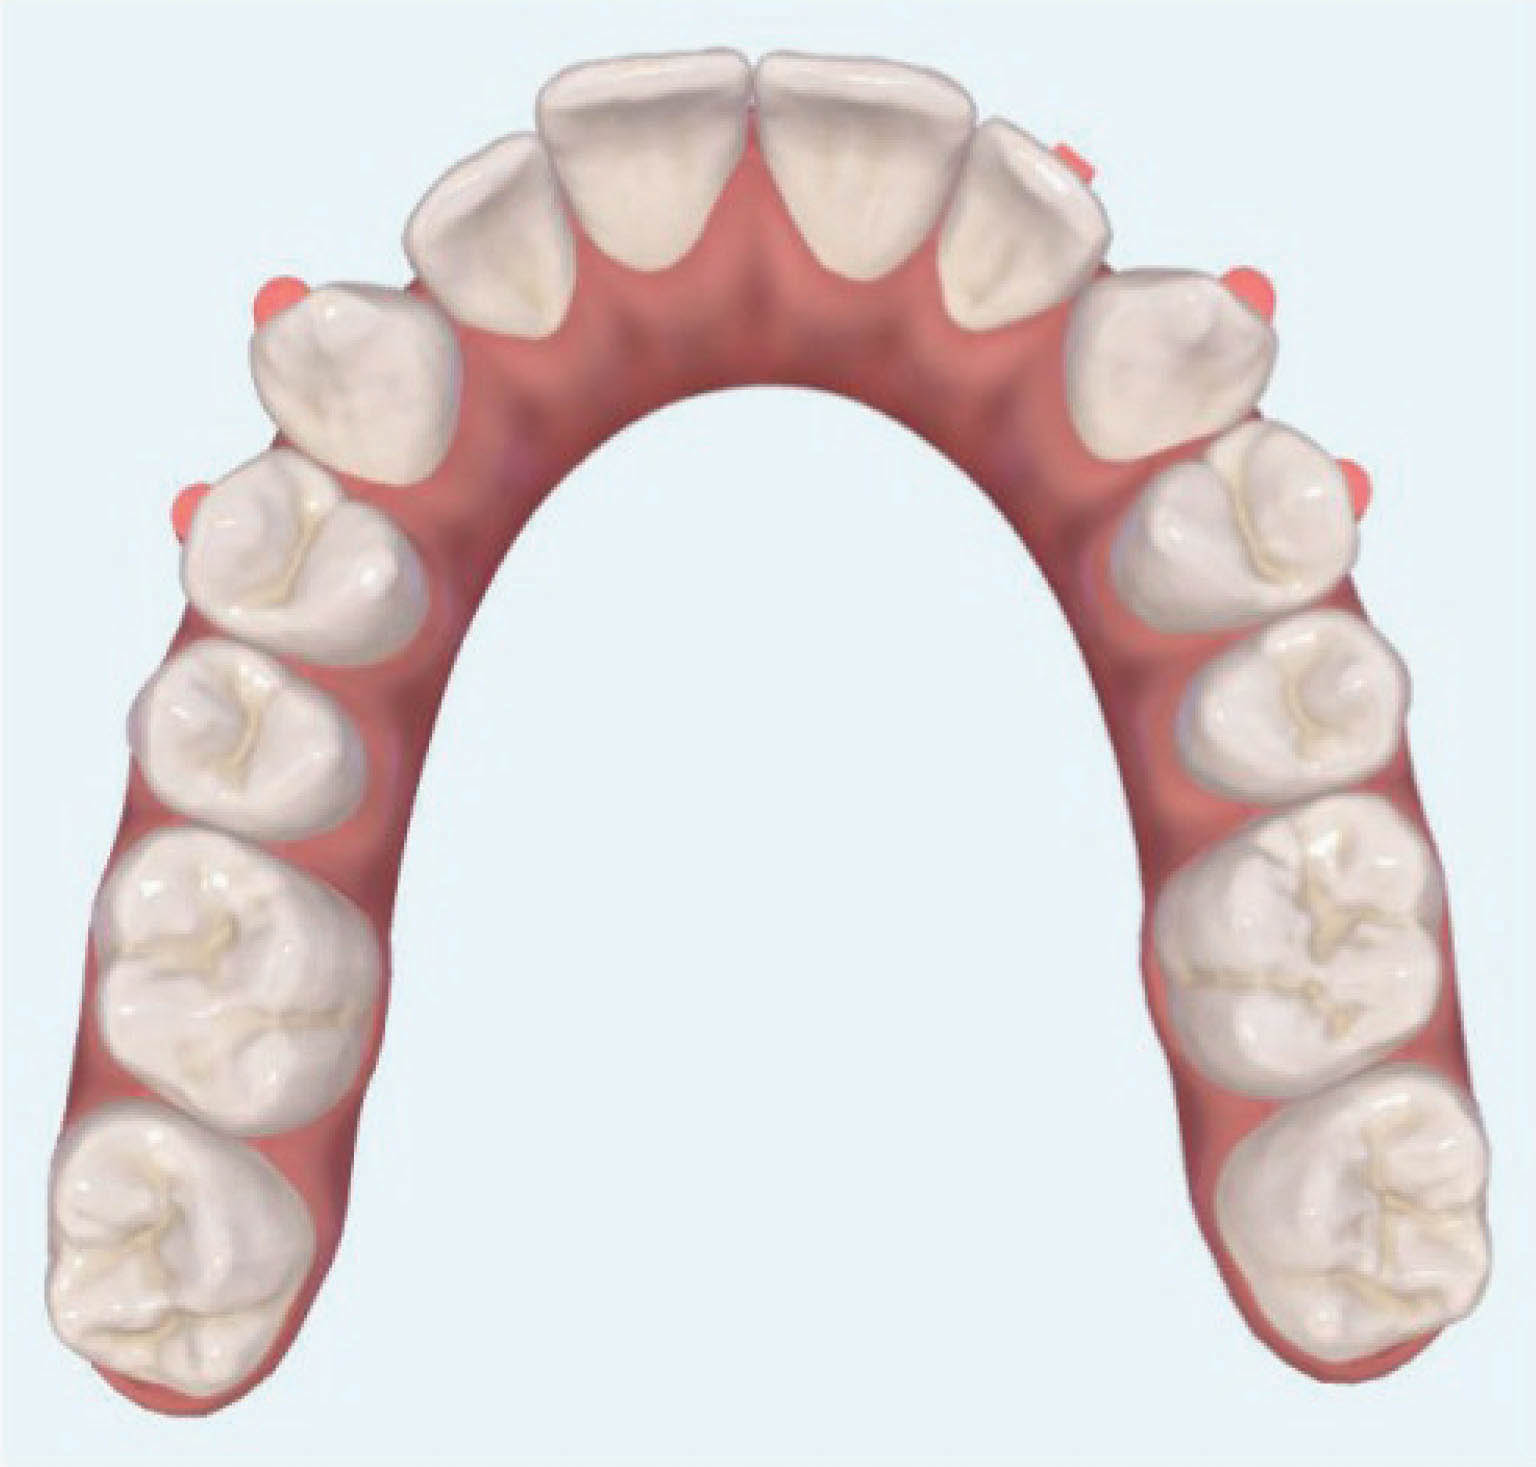

نتایج درمان (شکل 20-6) و عکس طراحی کامپیوتری (شکل 21-6) خیلی به هم شبیه شدند. عکس OPG هم طبیعی است.

این نوع کار کردن میتواند برای اکثر بیماران شما که کرادینگ در حد متوسط دارند و غیرکشیدنی میخواهید درمان نمایید به کار برود. اول به اکسپنشن خلف، بعد پروترود نمودن انسیزورها و نهایتاً به استریپ فکر کنید تا سرانجام دندانها به زیبایی ردیف گردند. لطفاً به یاد داشته باشید اگر میخواهید از پرمولرها استریپ کنید باید حتماً در دستور کار طراحی " استریپ خلفی" را ذکر کنید.

شکلهای 33-6 و 34-6 نتایج درمان را نشان میدهد. قوس فکی کاملاً مرتب شده است. عرض بین کانینی حفظ شده، اکستروژن نسبی لترال بالا را داریم و به نتایج زیبایی و فانکشنال خوبی رسیدیم.